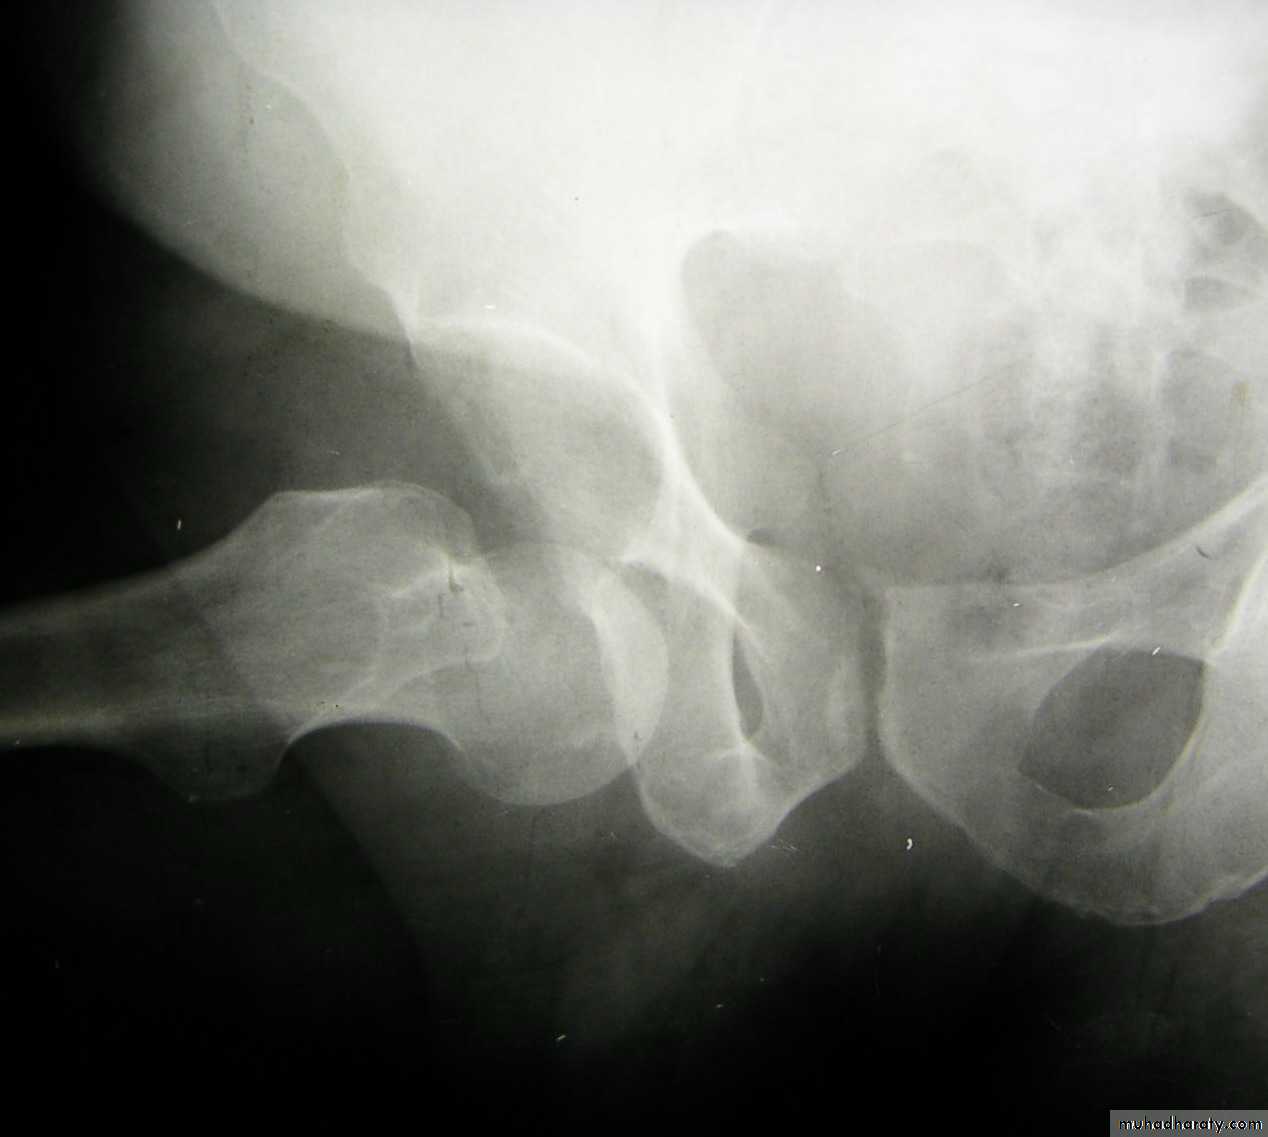

Inter-trochanteric fractures (extracapsular fracture)

.It is extra capsular fracture occurs in elderly..Unite quite easily and seldom cause a vascular necrosis.

The crack runs up between the lesser and greater trochanter.

Pathological anatomy divided into:

Stable:Unstable are those where

a. posteriomedial cortex is shattered.b. poor contact between fracture segment.

Radiological examination

2 typesStable.

Unstable.